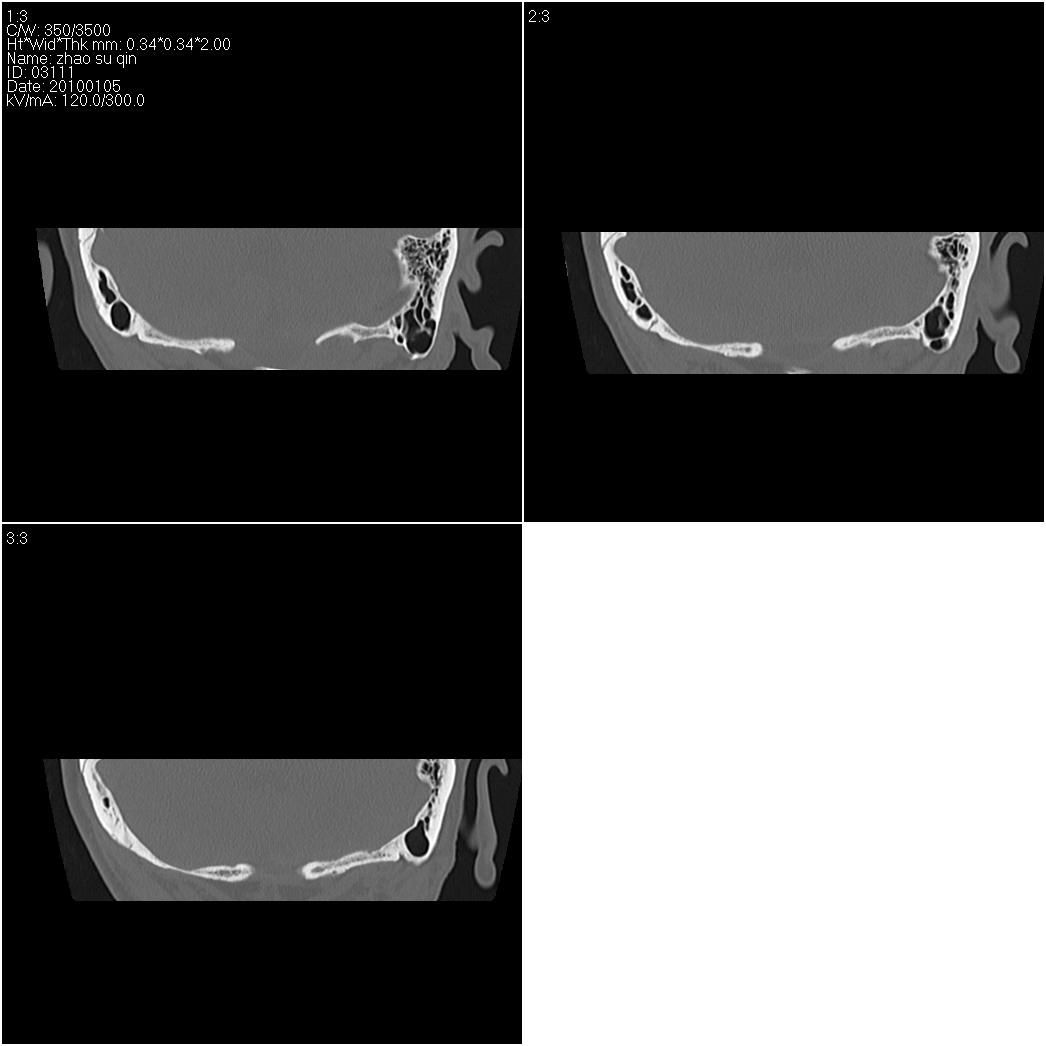

标题: CT24015:一个头部外伤患者进行鉴定,除了左侧筛板骨折,哪 [打印本页]

标题: CT24015:一个头部外伤患者进行鉴定,除了左侧筛板骨折,哪

看了几遍,其余未见明显骨折征。

其余未见明显骨折征。